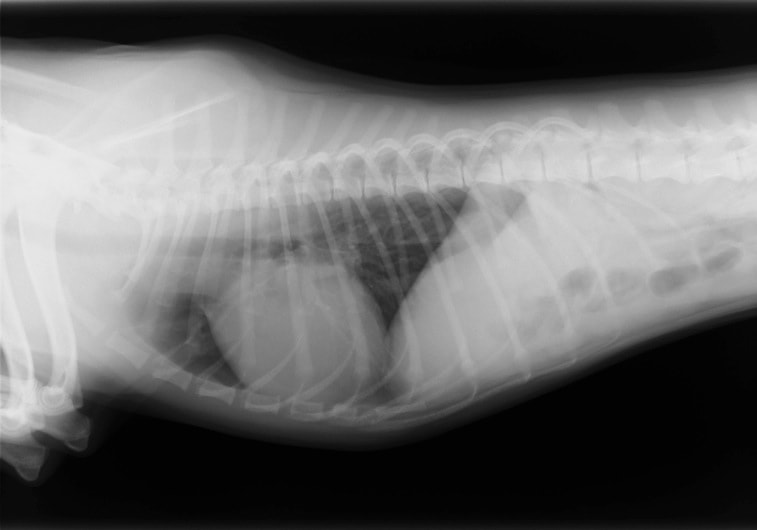

E:胸部レントゲン写真 側面像

左側胸壁心尖部領域を最強点とするLevine 5/6の収縮期性心雑音が聴取された。

胸部レントゲン検査において重度の心拡大と肺水腫が認められた。超音波検査では、重度の僧帽弁閉鎖不全症、三尖弁閉鎖不全症、中程度の大動脈弁閉鎖不全症を合併していることが判明した。三尖弁逆流速度から肺高血圧症が示唆された。

ACE阻害薬、ピモベンダン、硝酸イソソルビド徐放剤、ベラプロストナトリウム、利尿剤としてフロセミドとスピロノラクトンを用いて治療を行った。